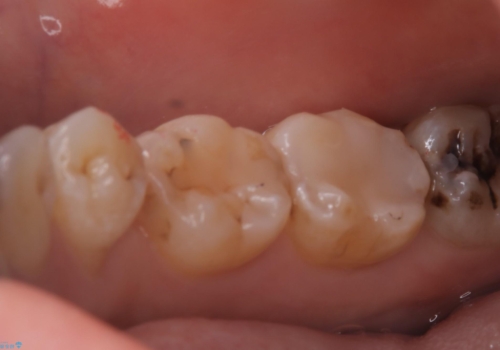

左下7番咬合面にコンポジットレジン修復されてり、経年劣化による着色や歯質との境目にう蝕を認め、セラミックインレーでのやり替えとなりました。

左下7番咬合面にコンポジットレジン修復されてり、経年劣化による着色や歯質との境目にう蝕を認めました。

コンポジットレジンとセラミックの物性的特徴を説明し、セラミックインレーでのやり替えとなりました。